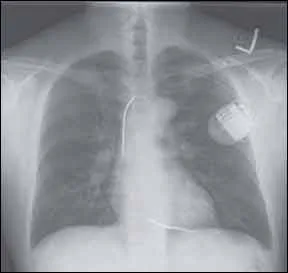

The decision to implant a cardiac device such as an implantable cardioverter defibrillator (ICD) is one that involves a thorough assessment of the patients overall health and his risk of sudden cardiac arrest (SCA). ICDs help patients at risk of recurrent and sustained ventricular tachycardia (a rapid heartbeat) or fibrillation (rapid, but irregular heartbeat), by sending electrical signals to the heart to help restore it to a normal rhythm. SCAs claim more lives in the U.S. than any other medical condition, including breast cancer, lung cancer and AIDS.